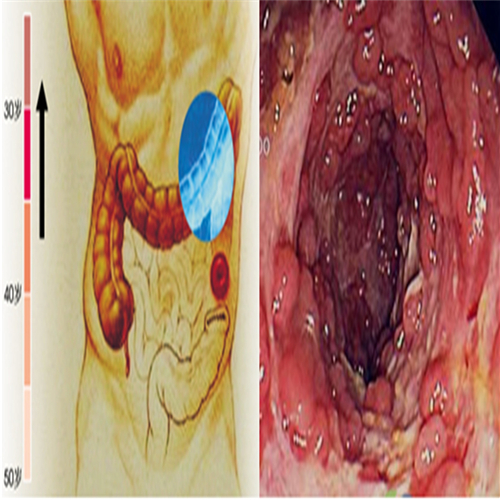

直腸息肉的症狀

直腸息肉惡變細胞